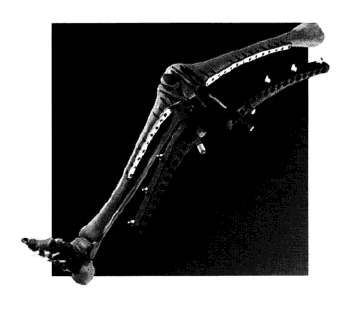

股骨干粉碎性骨折用梯形加压钢板治疗情况

A.术前;B术后6周;C.术后2年拆除钢板后